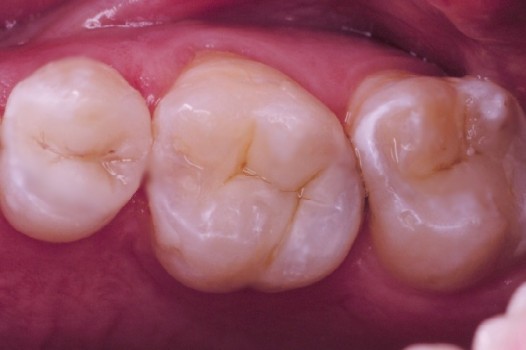

Traditional amalgam (mercury) fillings have been used for over a century, but concerns about health risks, tooth fractures, and long-term decay have led many dentists to adopt modern alternatives. Today, metal-free restorations offer healthier, stronger, and more natural-looking results.

Using advanced resins, ceramics, and state-of-the-art bonding techniques, Dr. Klim can restore teeth with precision, preserving healthy tooth structure while preventing fractures, bacterial invasion, and future toothaches.